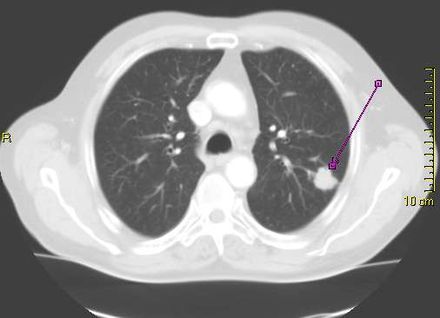

CT scan showing a cancerous tumor in the left lung